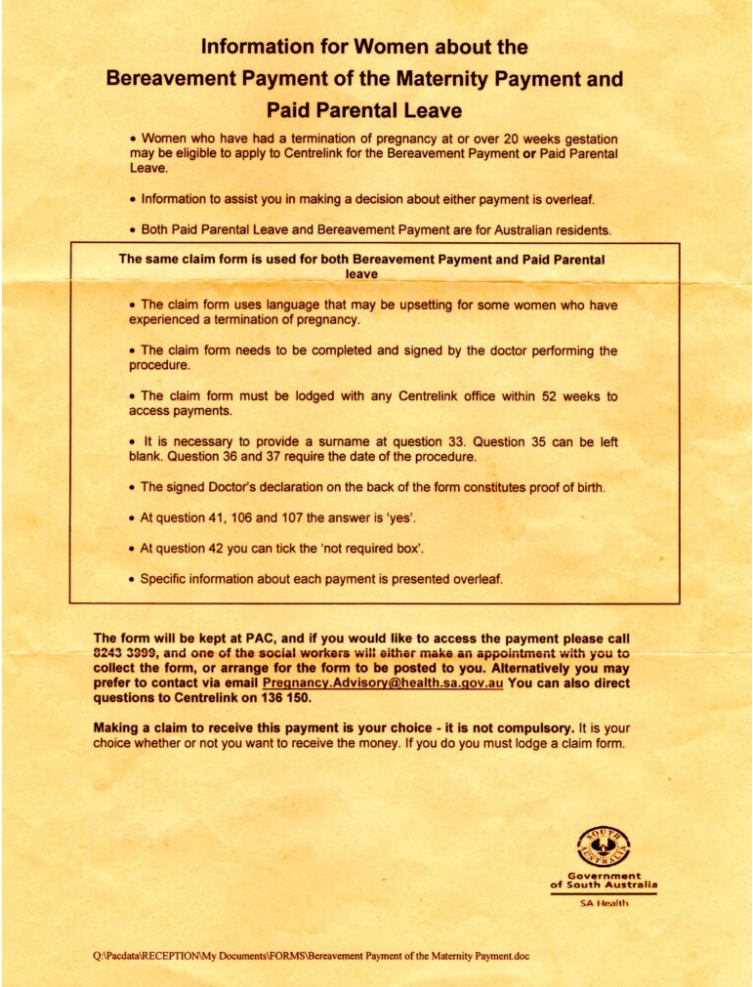

1. Centrelink’s definition of a stillbirth

As Dr Howe highlighted in her video, Centrelink’s broad definition of a stillbirth is the means by which people are accessing their aborted baby bonus.

The Services Australia website explains that “to be eligible for our payments, a stillbirth needs to meet our definition” — and their definition is as follows:

A late-term abortion — which, in Australia, is most often performed by injecting the baby’s heart with potassium chloride or digoxin, followed by the induction of labour and the delivery of the dead infant — clearly meets that definition.

Dr Howe’s key contention is that Services Australia has no carve-out to say the stillbirth has to be natural as opposed to intentional. All that’s required is a letter from the hospital confirming that the baby was delivered stillborn.